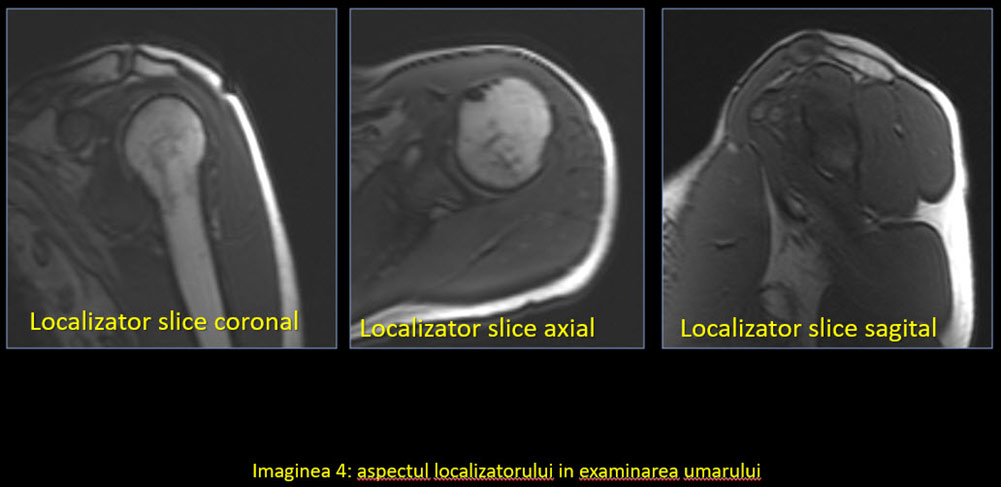

În mod normal, planurile uzual utilizate în imagistică sunt coronal, sagital și axial. În cazul umărului și majorității articulațiilor, oasele și articulațiile au o orientare specială, astfel încât se folosesc planuri modificate. Singurul plan standard este cel axial, deși poate suferi și el modificări în anumite condiții.